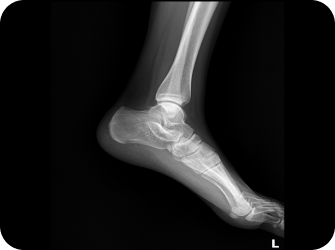

검사 프로세스

경골 및 종골 각도 검사

엑스레이 및 CT

다리 길이 엑스레이 검사